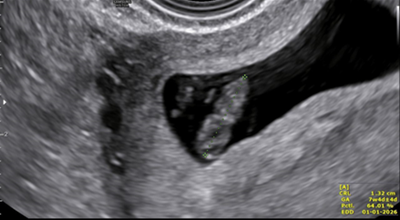

The case of a 27-year-old primiparous women who presented at 7 weeks with features of hyperemesis in a routine pregnancy follow up is presented. No previous ultrasonographic imaging was done. Current ultrasound scan showed a twin live intrauterine pregnancy with thick separating membrane giving a lambda sign. Crown Rump Length (CRL) of fetus A measured 1.32 mm with Fetal Heart Rate (FHR) at 166 Beats Per Minute (BPM) and the CRL of fetus B was 1.15 mm with FHR 154 BPM. It also showed a gestational sac with a fetal pole with CRL 10 mm in the right ovary complicated by a surrounding peri-ovarian hematoma forming a right adnexal mass measuring 57×35 mm. No cardiac activity was seen in this fetal pole (Figure 1 A/B).